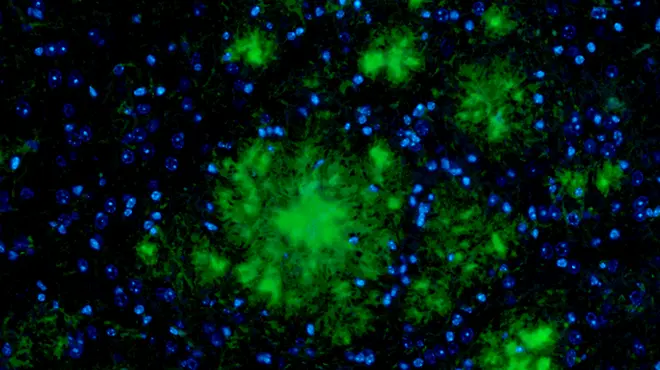

Neuroscientists restore cell-to-cell signaling and sociability in autism models